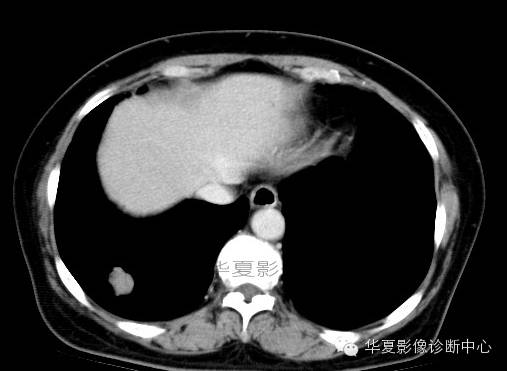

影像资料:

术中切除(右下)部分肺组织7x6x2cm,切面见一灰白色肿物,直径2cm,质较脆,与周围组织界限清,略呈分叶状,无包膜。

(右下肺)错构瘤(以软骨成份为主)

肺错构瘤多发生在胸膜下肺表浅部位,呈球形、椭圆形,有完整的包膜,质硬,易与周围肺组织分开。肺错构瘤的直径0.5~12cm,多数小于3cm。肿瘤剖面呈灰白色,质硬,有黏液和囊腔。主要成分有软骨、腺体、平滑肌、脂肪及纤维组织等。肿瘤可发生钙化,多位于中心,分布较均匀,此种钙化结构常像爆米花样或核桃肉样。